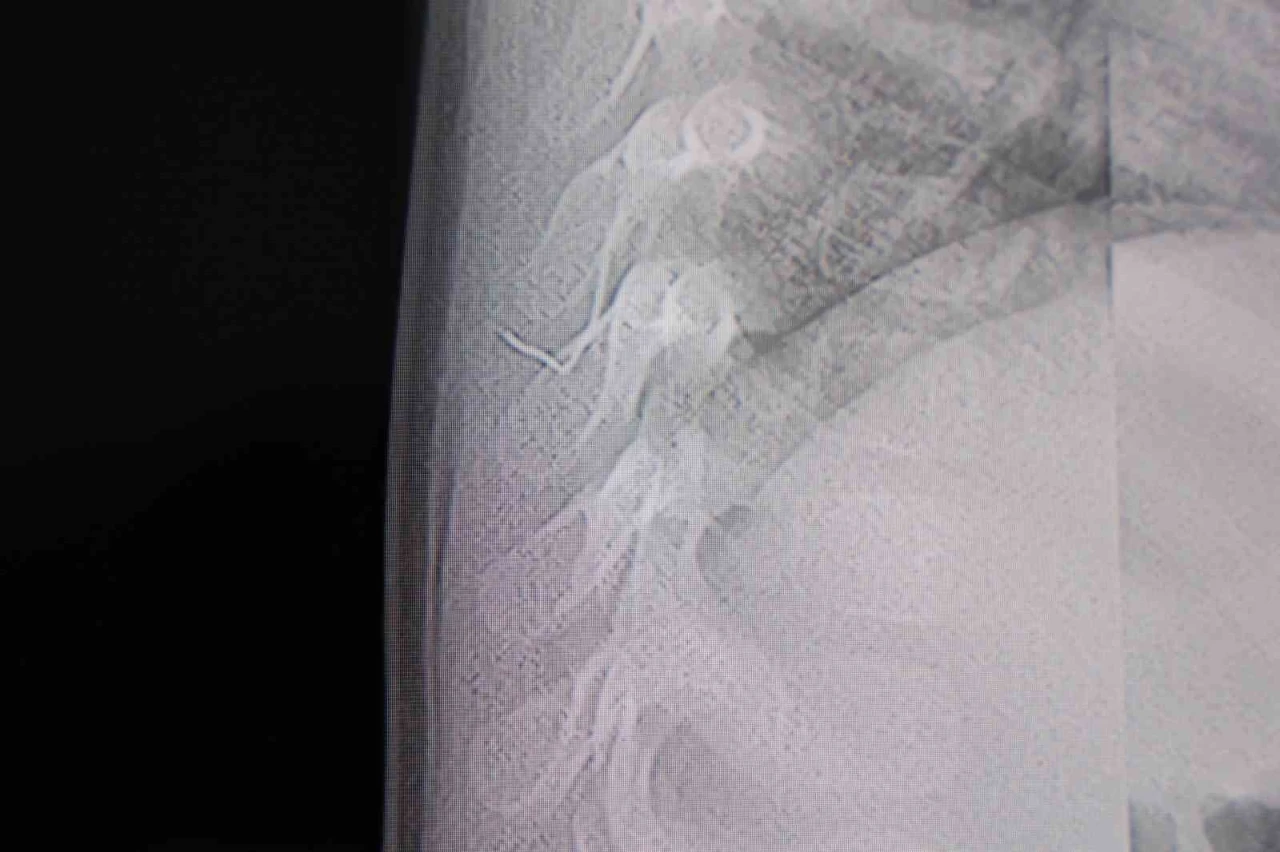

Kahramanmaraş’ta sırt üstü yatmak istemeyen, yatırıldığında ağlama ve huzursuzluğu nedeniyle hastaneye götürülen bir yaşındaki bebeğin sırtından akciğer zarına doğru ilerleyen 2 santimetrelik zımba teli çıktı.

Aile, bebekleri için son olarak HG Hospital’e başvurdu. HG Hospital Beyin ve Sinir Cerrahisi Uzmanı Prof. Dr. İdris Altun tarafından yapılan tetkiklerde, yabancı cismin cilt altında, omurilik kanalına yakın bir bölgede olduğu ve Akciğerzarına doğru ilerlediği belirlendi. Hasta, genel anesteziye alınmadan, lokal anestezi ve sedasyon eşliğinde ameliyata alındı. Yapılan müdahalede yabancı cisim tamamen çıkarıldı. Çıkarılan cismin, ince zımba teline benzer metal bir tel olduğu ve yaklaşık 2 santimetre uzunluğunda bulunduğu tespit edildi. Hasta, aynı gün taburcu edildi.

Konuya ilişkin açıklama yapan Prof. Dr. İdris Altun, "Sırtında yabancı bir cisim olduğu söylenmiş ancak çıkarılamayacağı ve 8 yaşına kadar beklenmesi gerektiği ifade edilmişti. Bize başvurduğunda yaptığımız tetkiklerde, cilt altında, omurilik kanalına çok yakın ve akciğer zarına doğru ilerleyen bir yabancı cisim tespit ettik. Hastamızı tamamen uyutmadan, lokal anestezi ve sedasyon eşliğinde müdahale ederek lezyonu tamamen çıkardık. Çıkardığımız cismin ince zımba teline benzer, yaklaşık 2 santimetre uzunluğunda metal bir tel olduğunu gördük. Bu yabancı cisim alınmasaydı, bölgede enfeksiyon gelişebilirdi. Enfeksiyon sonucu omurilik kanalında ciddi hasarlar oluşabilir, çocuk büyüdükçe cismin hareket etmesine bağlı olarak omurilikte zedelenmeler meydana gelebilirdi. Ayrıca yana doğru ilerleyerek akciğer zarına ve akciğere batma riski vardı. Bu da enfeksiyona ve ilerleyen süreçte tümörle karışabilecek tablolara neden olabilirdi. Şu an hastamız gayet sağlıklı. Gerekli kontrolleri yaptık ve aynı gün taburcu ettik" dedi.